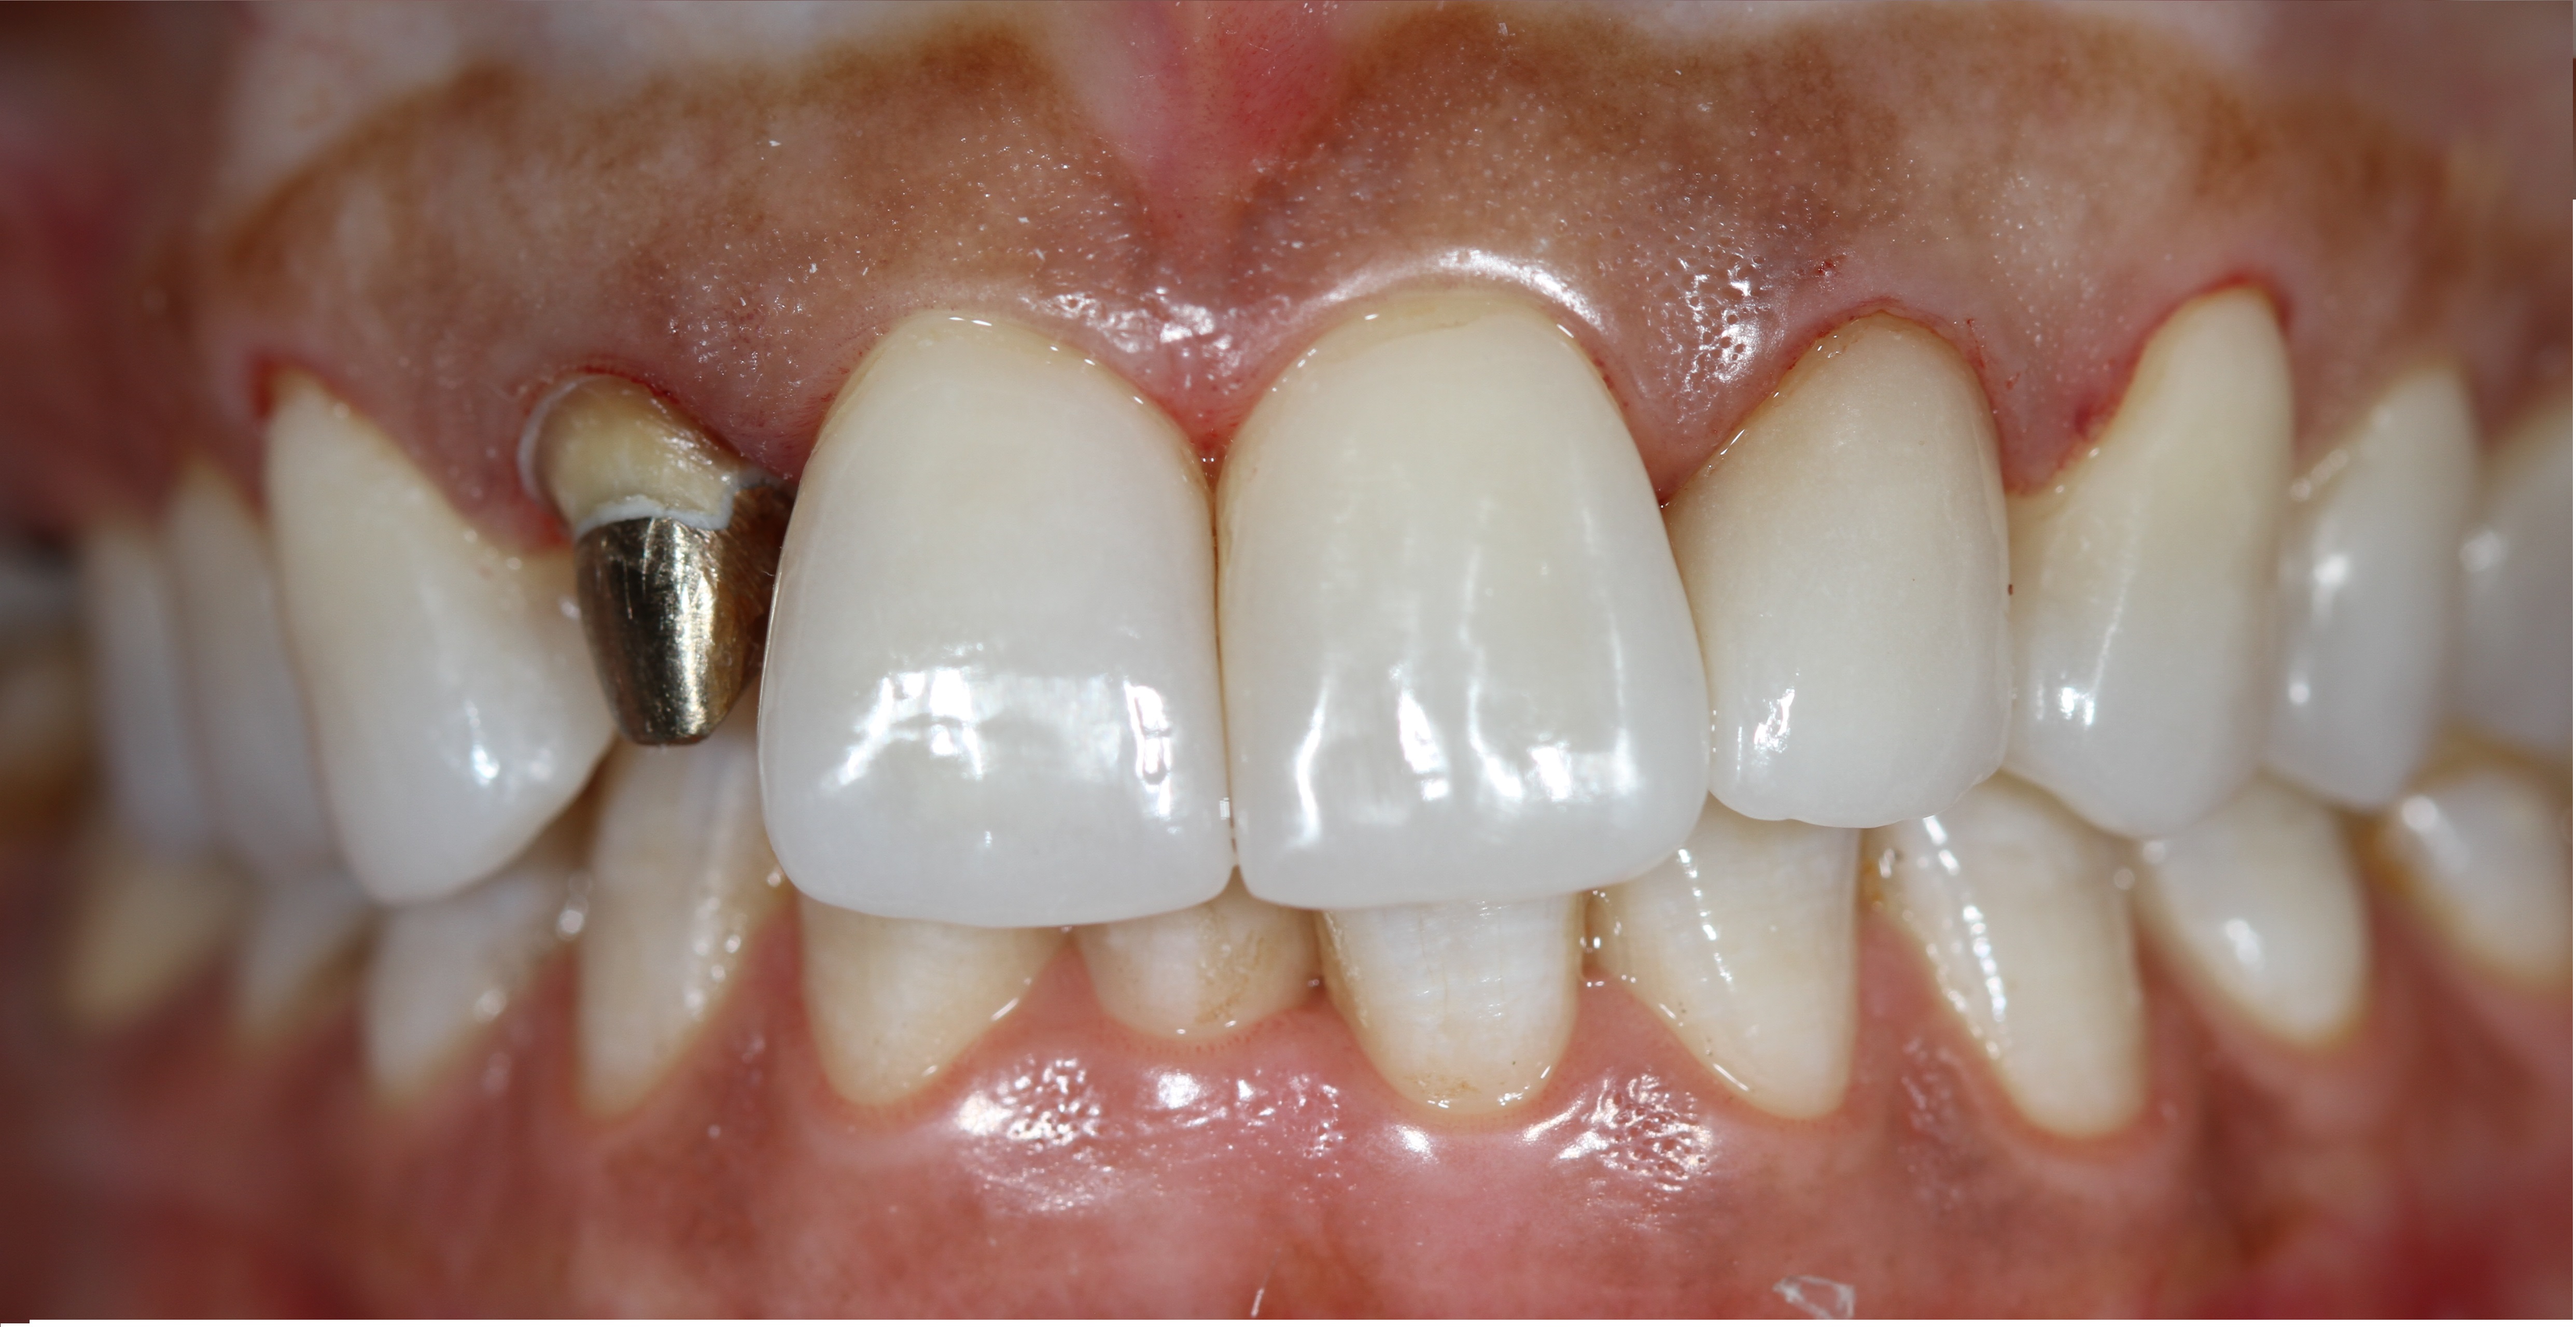

Белые виниры BLEACH

Все чаще стали поступать заказы на виниры цвета BLEACH. Очень красивый результат. Улыбка становится очень красивой.

Это виниры на рефракторе . 12 зуб коронка на оксиде циркония.